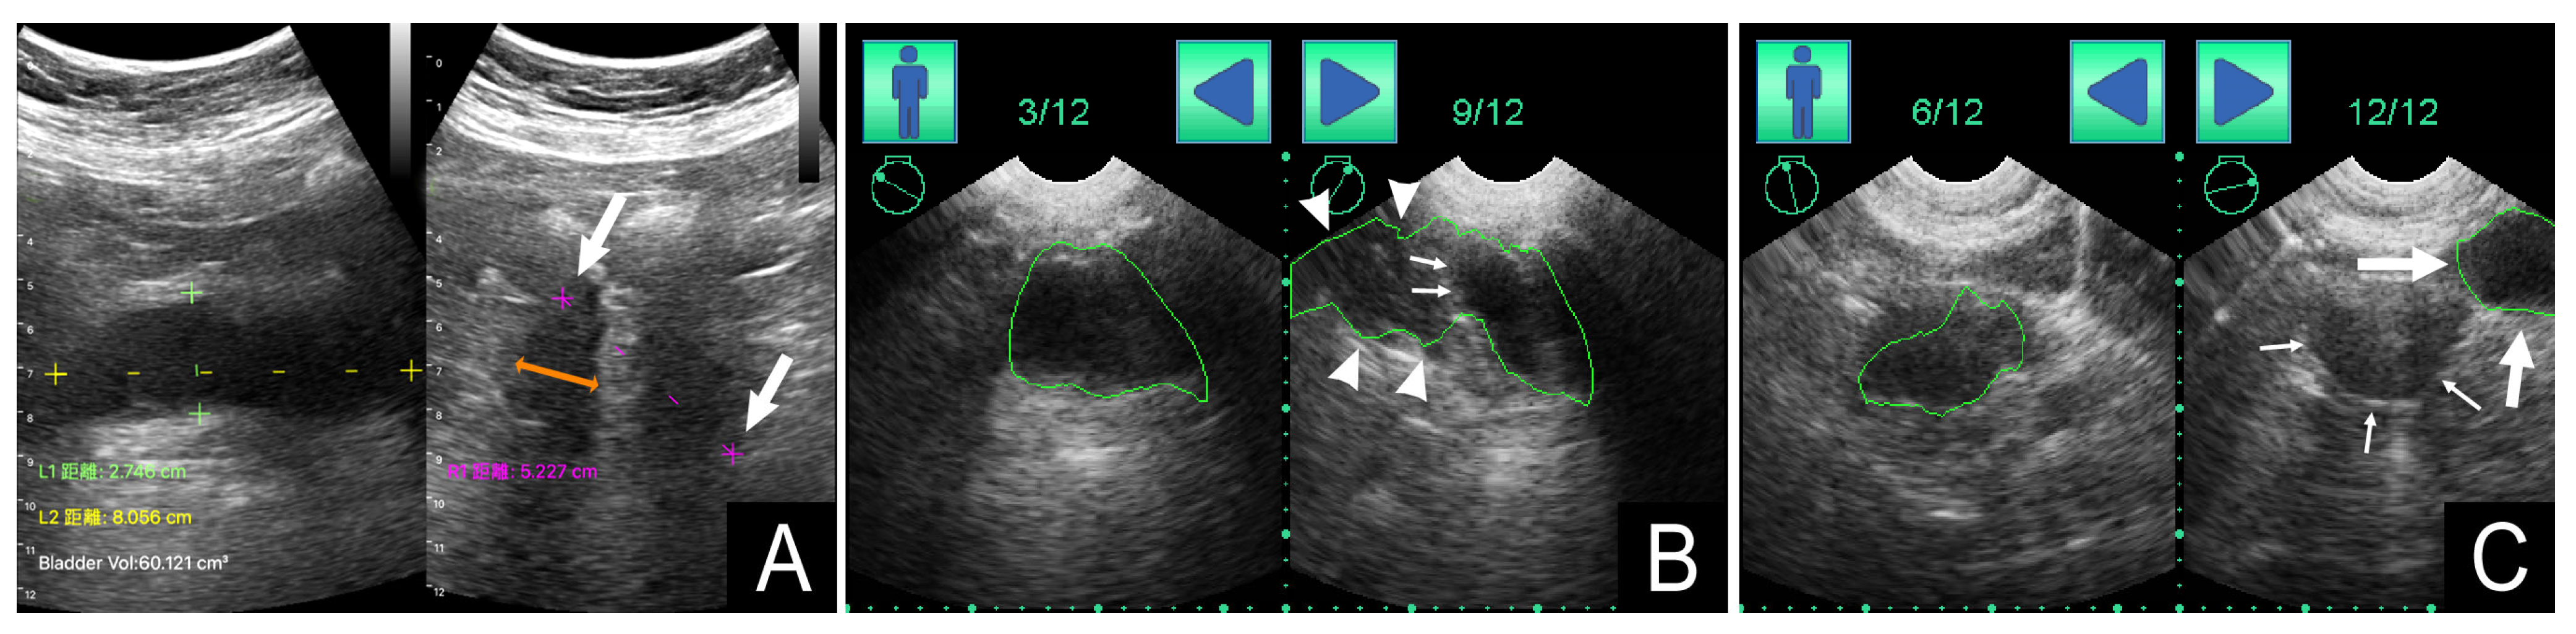

| PVRU Volume (mL) | Measurement Deviations | Gender | ||||

| Bladder Shape | Device A (n = 108) | Device B (n = 108) | Device A (n = 11) | Device B (n = 43) | Women (n = 64) | Men (n = 44) |

| Spherical (n = 32) | 26 (12–46) | 26 (10–67) | 1 (3%) | 13 (41%) | 23 (72%) | 9 (28%) |

| Triangular (n = 24) | 43 (26–74) | 71 (46–105) | 2 (8%) | 9 (38%) | 16 (67%) | 8 (33%) |

| Undefined (n = 11) | 61 (40–91) | 89 (49–152) | 4 (36%) | 6 (55%) | 6 (55%) | 5 (45%) |

| Ellipsoid (n = 18) | 135 (114–159) | 204 (141–276) | 3 (17%) | 7 (39%) | 5 (28%) | 13 (72%) |

| Cuboid (n = 23) | 188 (124–257) | 317 (244–386) | 1 (4%) | 8 (35%) | 15 (65%) | 8 (35%) |

| p value | <0.001 * | <0.001 * | 0.019 ** | 0.860 ** | 0.033 ** | |